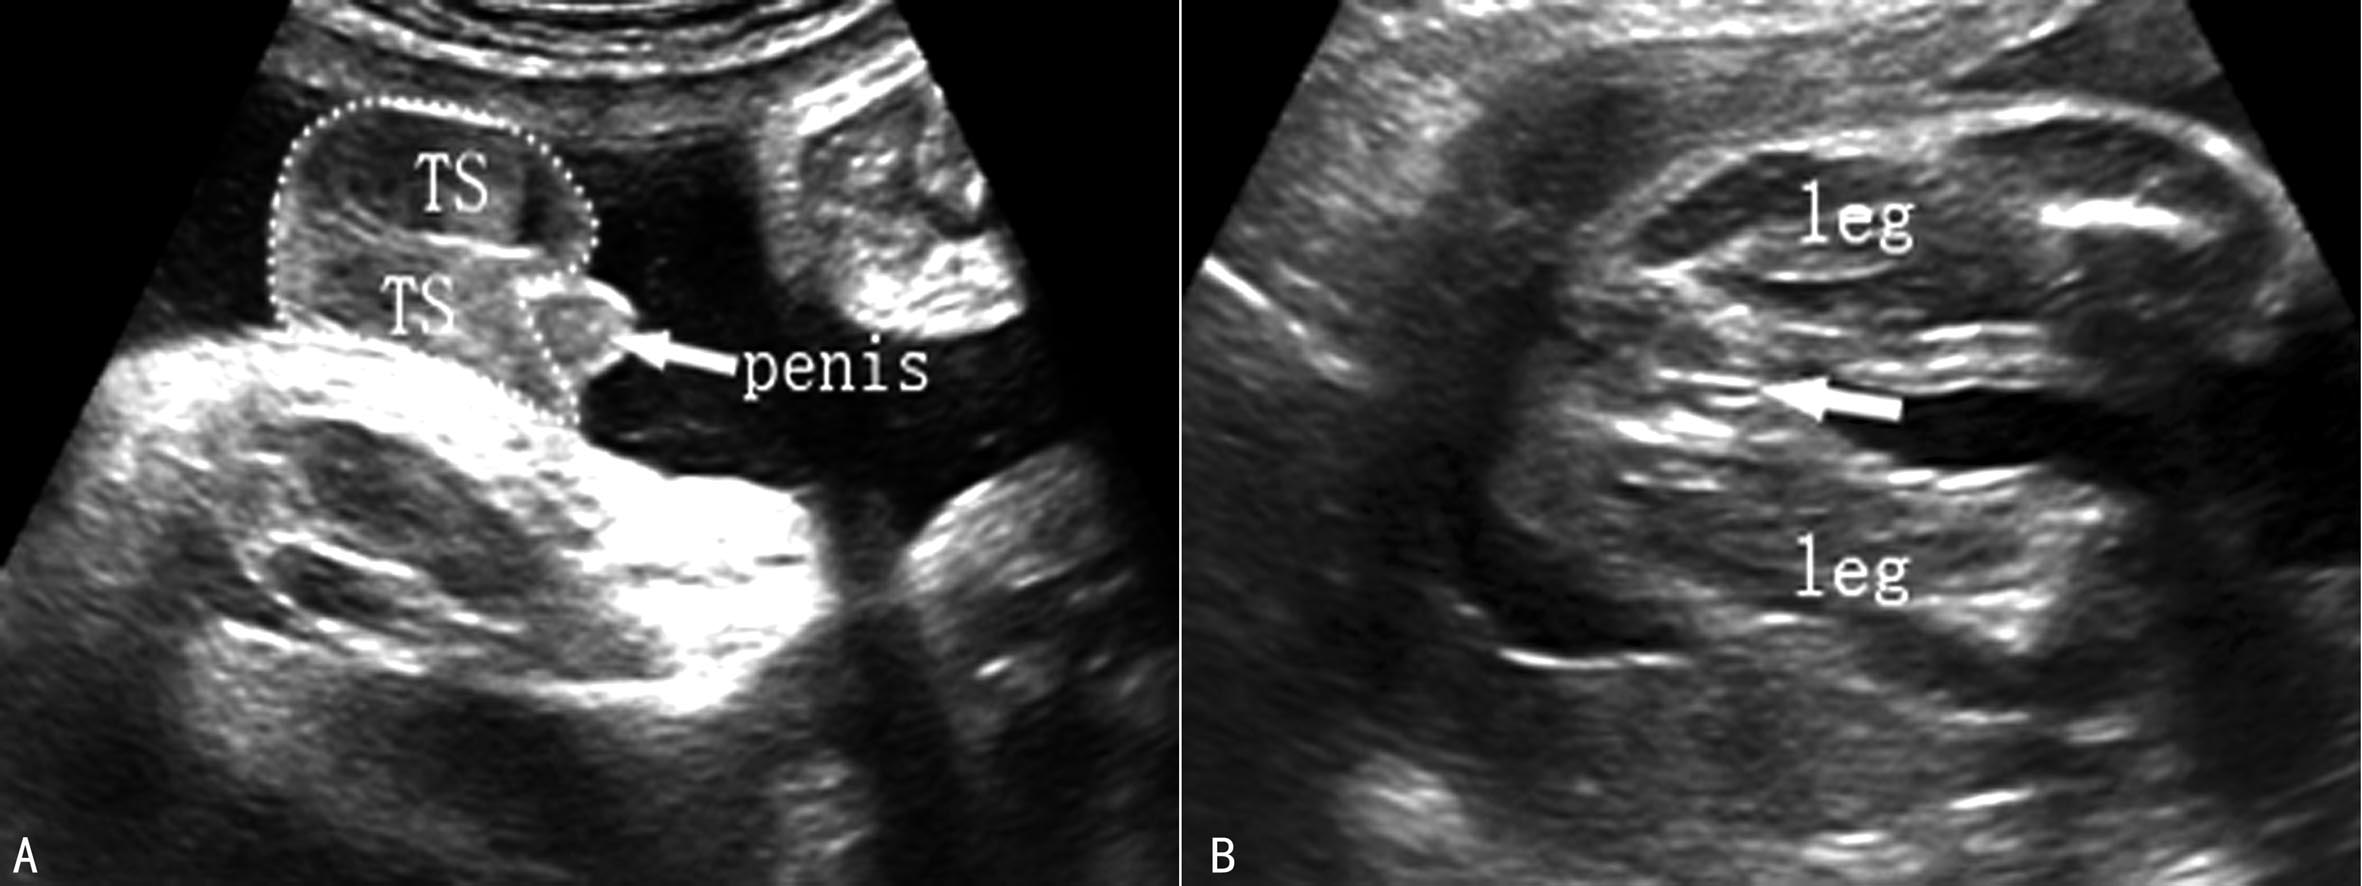

4.胎儿外生殖器 男性外生殖器较女胎的易显示。男性外生殖器可显示阴囊、*丸睾**、阴茎(图8A)。注意不要将两腿间的脐带、手指、腹腔外的肠道(脐疝或腹裂所致)误作为阴茎或阴囊。孕18周后,阴囊和阴茎可清晰显示。孕22周后,大阴唇可清晰显示(图8B)。

图8外生殖器声像图